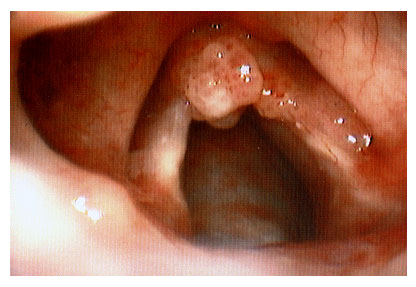

A papilomatose laríngea, uma condição que pode afetar a qualidade de vida e a saúde vocal, exige atenção especial à nutrição. Em 2026, entendemos que uma dieta bem planejada não é apenas um coadjuvante, mas um pilar fundamental no manejo e na busca pela erradicação do vírus HPV, o principal causador da doença. Focar em alimentos que fortalecem o sistema imunológico e que auxiliam na recuperação é um passo inteligente para quem convive com essa condição.

Referência: portaldootorrino.com

Fortalecer seu sistema imunológico é uma das estratégias mais eficazes para combater o HPV, o vírus por trás da papilomatose laríngea. Uma imunidade robusta ajuda seu corpo a combater a infecção e a reduzir a gravidade das lesões. Priorize alimentos frescos e naturais, repletos de vitaminas e minerais essenciais. Frutas cítricas, vegetais folhosos verde-escuros, e grãos integrais são excelentes pontos de partida. Eles fornecem os blocos de construção necessários para que suas defesas trabalhem de forma otimizada.

Como Fortalecer a Imunidade Naturalmente Contra o HPV

Referência: oldfiles.bjorl.org